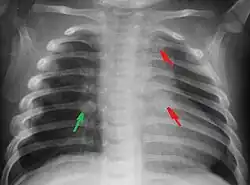

Rib fractures in an infant secondary to child abuse

The immediate physical effects of abuse or neglect can be relatively minor (bruises or cuts) or severe (broken bones, hemorrhage, death). Certain injuries, such as rib fractures or femoral fractures in infants that are not yet walking, may increase suspicion of child physical abuse, although such injuries are only seen in a fraction of children suffering physical abuse.[90][91] Cigarette burns or scald injuries may also prompt evaluation for child physical abuse.[92]